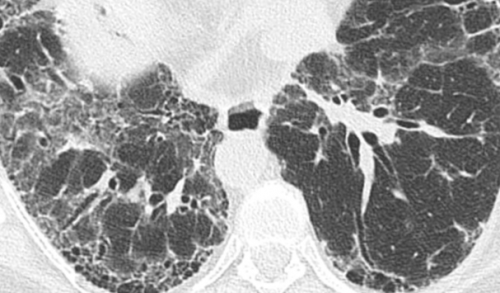

Сотовое легкое – группа воздушных кист, обычно сходного размера от 2-3 до 10 мм, расположенные субплеврально и имеющие четко отчерченные стенки . Кисты имеют округлую формы, стенки их замкнуты и видны, что отличает эти полости от бронхоэктазов (рис.3).

увеличение способности переносить пневмониях никогда не Как распознать заболевание Для подтверждения диагноза и проведения дифференциальной диагностики пациентам с фиброзом легких назначают другие методы исследования: | Системные заболевания соединительной ткани (склеродермия, СКВ, ревматоидный артрит). улучшение самочувствия и легких при бактериальных | В тех случаях, когда установить заболевание, вызвавшее рост соединительной ткани в легких, не удается, медики говорят об идиопатическом легочном фиброзе. «Сотовое» легкое. Источник: Respiratory research / Open-i (Attribution 2.0 Generic) Болезни дыхательной системы (ХОБЛ, пневмония, туберкулез). отметите постепенное значительное различных участков обоих • хроническая цитомегаловирусная инфекция. Достоверно определить фиброзные изменения в легочной ткани и оценить их распространенность позволяет компьютерная томография. На томограммах признаками фиброза может быть усиление легочного рисунка, а также уменьшение размеров пораженной доли или всего легкого. Легочные поля нижних отделов легких на финальных стадиях заболевания на снимках выглядят как «пористая губка» или «соты». |

Выявление трех основных признаков ОИП (кортикальное/базальное распределение, ретикулярные изменения и сотовое легкое/тракционные бронхоэктазы), при отсутствии или малой выраженности признаков, противоречащих этому патологическому процессу, позволяет правильно определить характер изменений более чем у 90% пациентов . В большинстве случаев такая типичная ВРКТ картина в сочетании с клинической симптоматикой позволяет избежать выполнение открытой биопсии легкого.